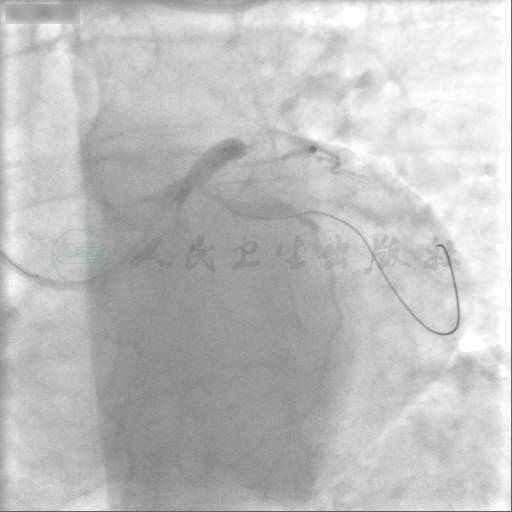

选用右侧桡动脉路径,6F血管鞘。造影发现:前降支近段狭窄90%伴原发撕裂,中段长病变狭窄80%,回旋支大OM开口完全闭塞,前降支经对角支至回旋支大OM2级侧支循环形成,右冠脉至回旋支大OM1~2级侧支循环形成(图1~图6)。

图5 右冠造影1

图6 右冠造影2